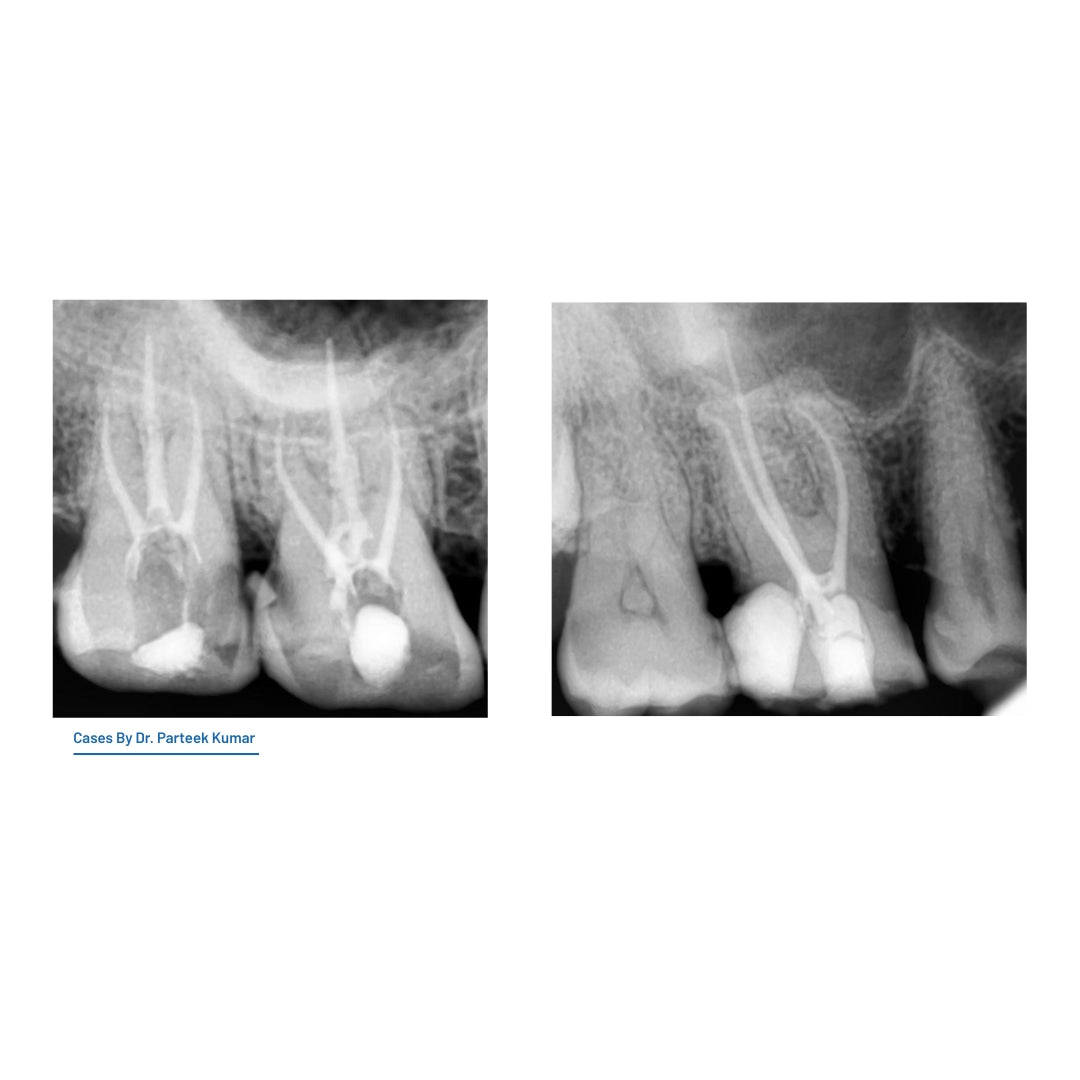

Aurum S Cross-Section File: Enhanced durability for curved canals.